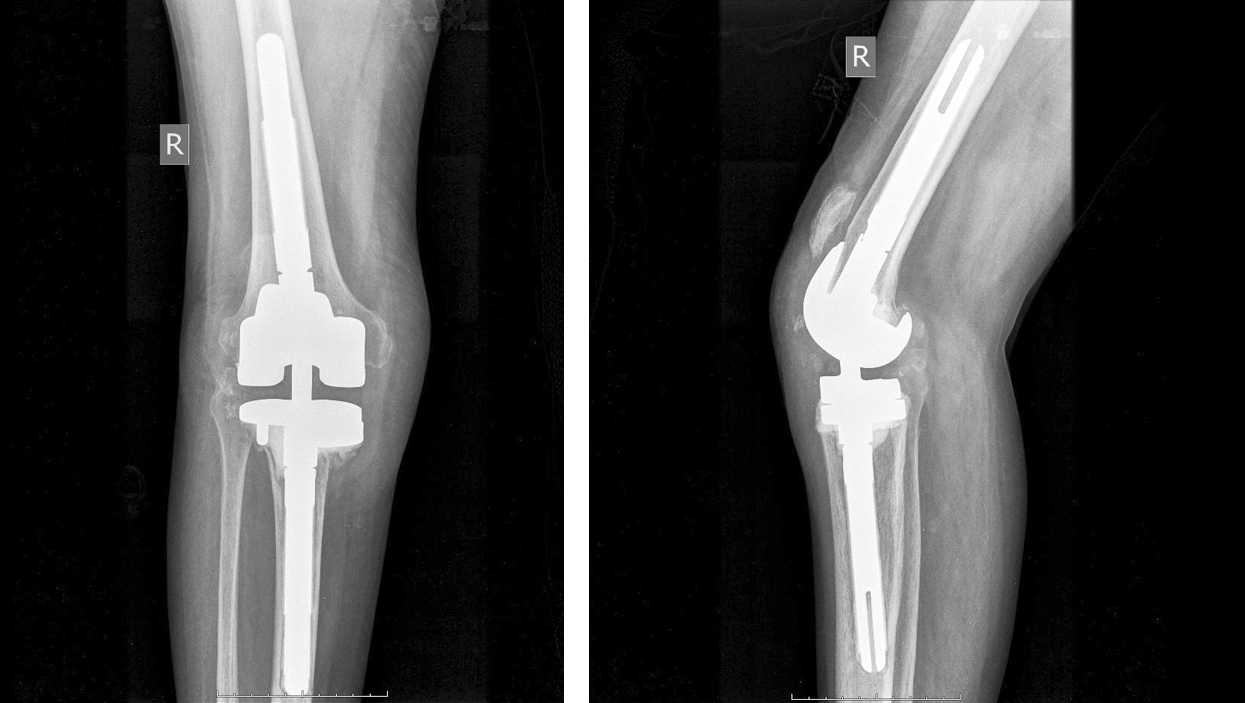

Спустя полгода пациентка госпитализирована в ортопедическое отделение для проведения второго этапа ревизионного эндопротезирования коленного сустава (рис. 2). При поступлении передвигалась на костылях без опоры на нижнюю конечность, длинные расстояния преодолевала с помощью инвалидной коляски. Укорочение конечности составляло 3 см, отмечались варусная деформация, несостоятельность медиальной коллатеральной связки, высокое положение надколенника (patella аlta), гипотрофия мышц правого бедра. Движения в правом коленном суставе болезненные, их амплитуда составляла 0/0/20°. Данные лабораторного обследования свидетельствовали о купировании инфекционного воспаления. Функциональное состояние по шкалам WOMAC и KSS было оценено как неудовлетворительное, уровень боли по визуально-аналоговой шкале (VAS) составил 8 баллов.

Рис. 2. Предоперационные рентгенограммы коленного сустава в прямой и боковой проекциях — установлен индивидуально изготовленный спейсер

Обширные дефекты большеберцовой кости типа 3 по классификации AORI потребовали установки индивидуально изготовленного имплантата проксимального метаэпифиза большеберцовой кости.